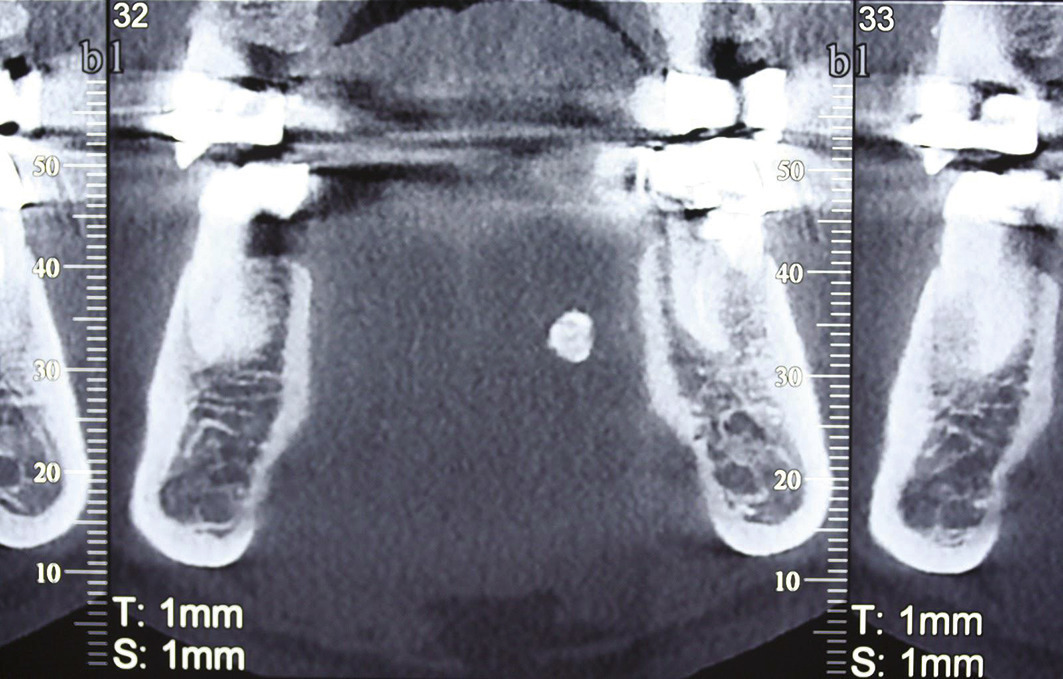

Le scanner

C’est un examen clé, de grande sensibilité et valeur localisatrice. C’est l’examen de choix. Il est le plus souvent effectué sans injection de produit de contraste. L’injection ne sera nécessaire qu’en cas de suspicion d’infection ou de tumeur (fig. 9).

Le cone beam

Cette tomographie volumique par faisceau conique est une technique de tomodensitométrie permettant de produire une radiographie numérisée. Cet examen peut remplacer le scanner car il est moins irradiant, moins coûteux, et présente moins d’artéfacts dentaires ; en revanche, il n’est pas pris en charge par l’Assurance maladie dans cette indication et montre mal les tissus mous (fig. 10).